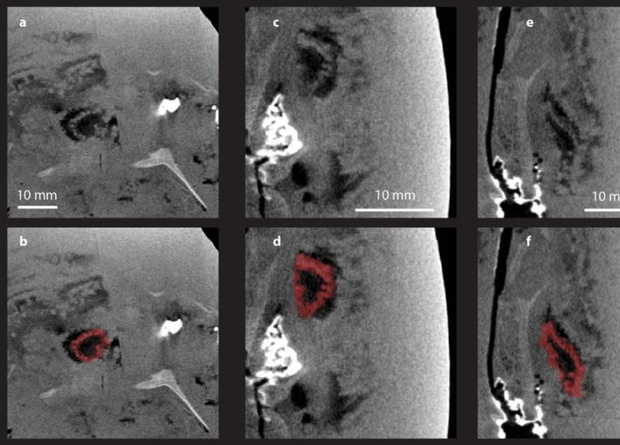

Палеонтологи обнаружили на австралийском местонахождении Гоугоу, возраст которого составляет 390-370 миллионов лет, окаменелости древних рыб плакодерм с хорошо сохранившимися внутренними органами, включая самые древние известные сердца. Как отмечается в статье для журнала Science, находка позволяет не только реконструировать строение плакодерм, но и лучше понять эволюцию челюстноротых — в том числе определить момент появления легких.

Местонахождения с исключительной сохранностью организмов, где можно обнаружить ископаемые с мягкими тканями, называют лагерштеттами консервационного типа. К ним относятся, например, сланцы Бёрджес в Британской Колумбии или Зольнхофен в Германии. Менее известный лагерштетт Гоугоу расположен в Австралии. На этом верхнедевонском местонахождении возрастом 390-370 миллионов лет были найдены многочисленные остатки древних рыб плакодерм (Placodermi) (или, как их называли раньше, панцирных рыб)